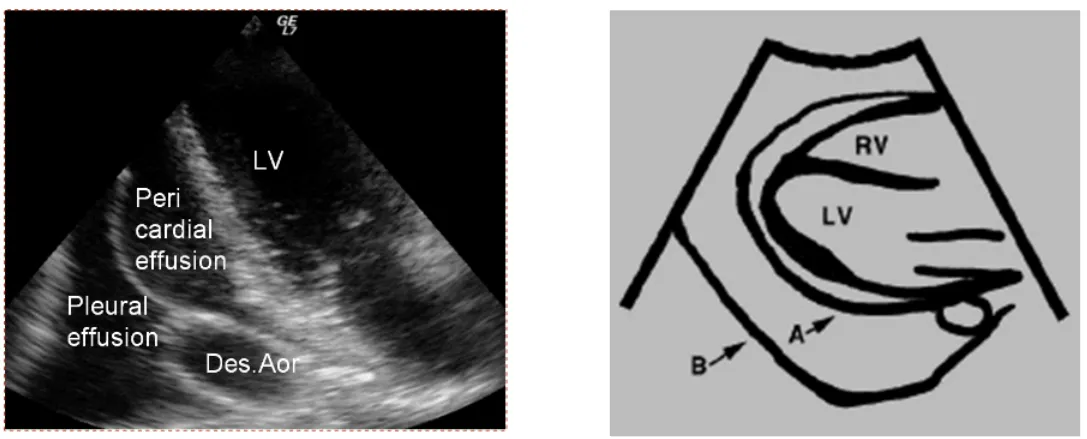

(1) pericardial effusion이 맞는지 확인

-> Aorta와 LV 사이에 나오는게 Pericardial effusion이고 그 뒤에 있는건 Pleural effusion.

또한 epicardial fat pad도 감별. Fat pad는 주로 앞쪽에서만 보이고 effusion은 앞뒤로 둘러싸고 있음.